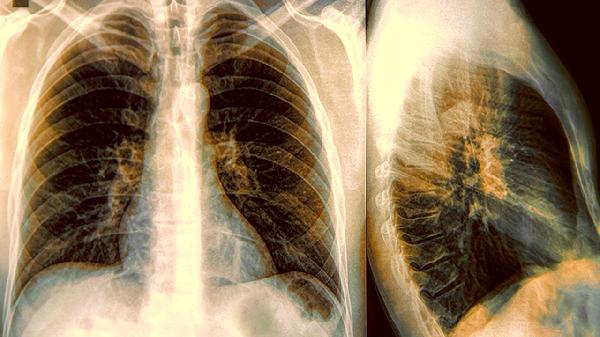

该药含有的桔梗、前胡等成分能宣肺化痰,缓解肺热壅盛导致的咳嗽痰黄、胸闷气促。对于支气管炎、肺炎等疾病伴随的黏稠痰液有一定化解作用。服用期间应保持室内空气流通,多饮温水帮助稀释痰液。